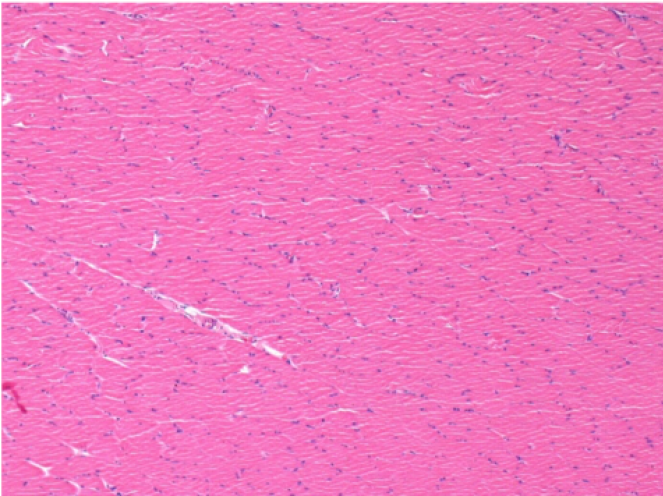

3 mesi dopo Iniezione di Endopeel

3 mesi (Giorno90) dopo iniezione 0.1ml di Endopeel nel muscolo pretibiale destro ( Dx)

Sx : Controllo-100x-Giorno90

Dx:100x-Giorno90